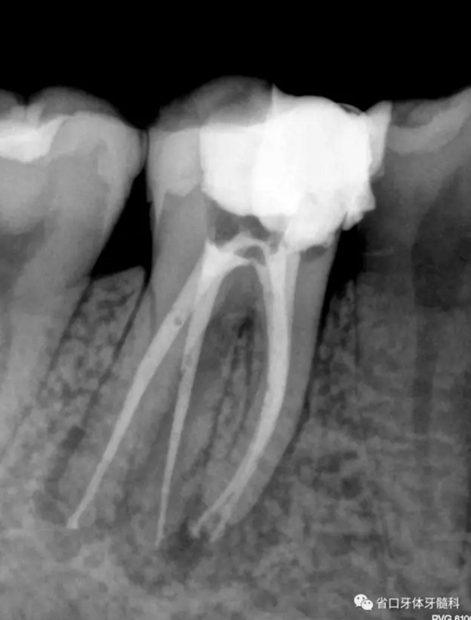

圖2 術(shù)后根充片

術(shù)后隨訪x線片,遠(yuǎn)頰、遠(yuǎn)舌根尖低密度影消失,近頰根尖低密度影局限(提示近頰根尖瘢痕愈合),嵌體不阻射x線。